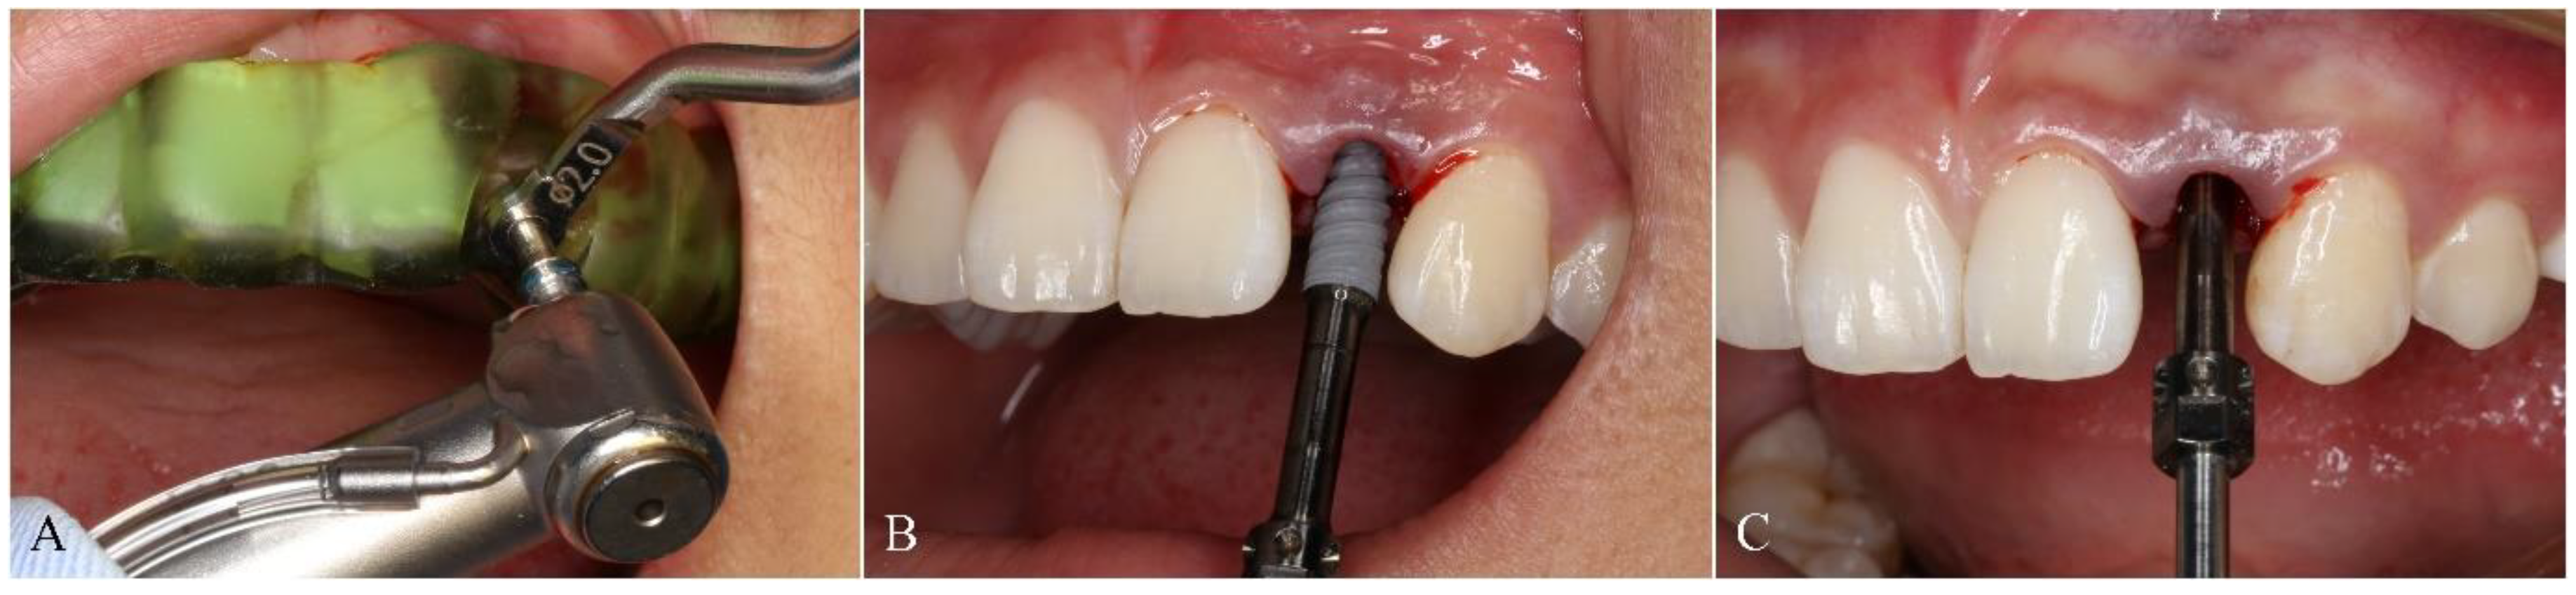

2.4. Surgical Procedure